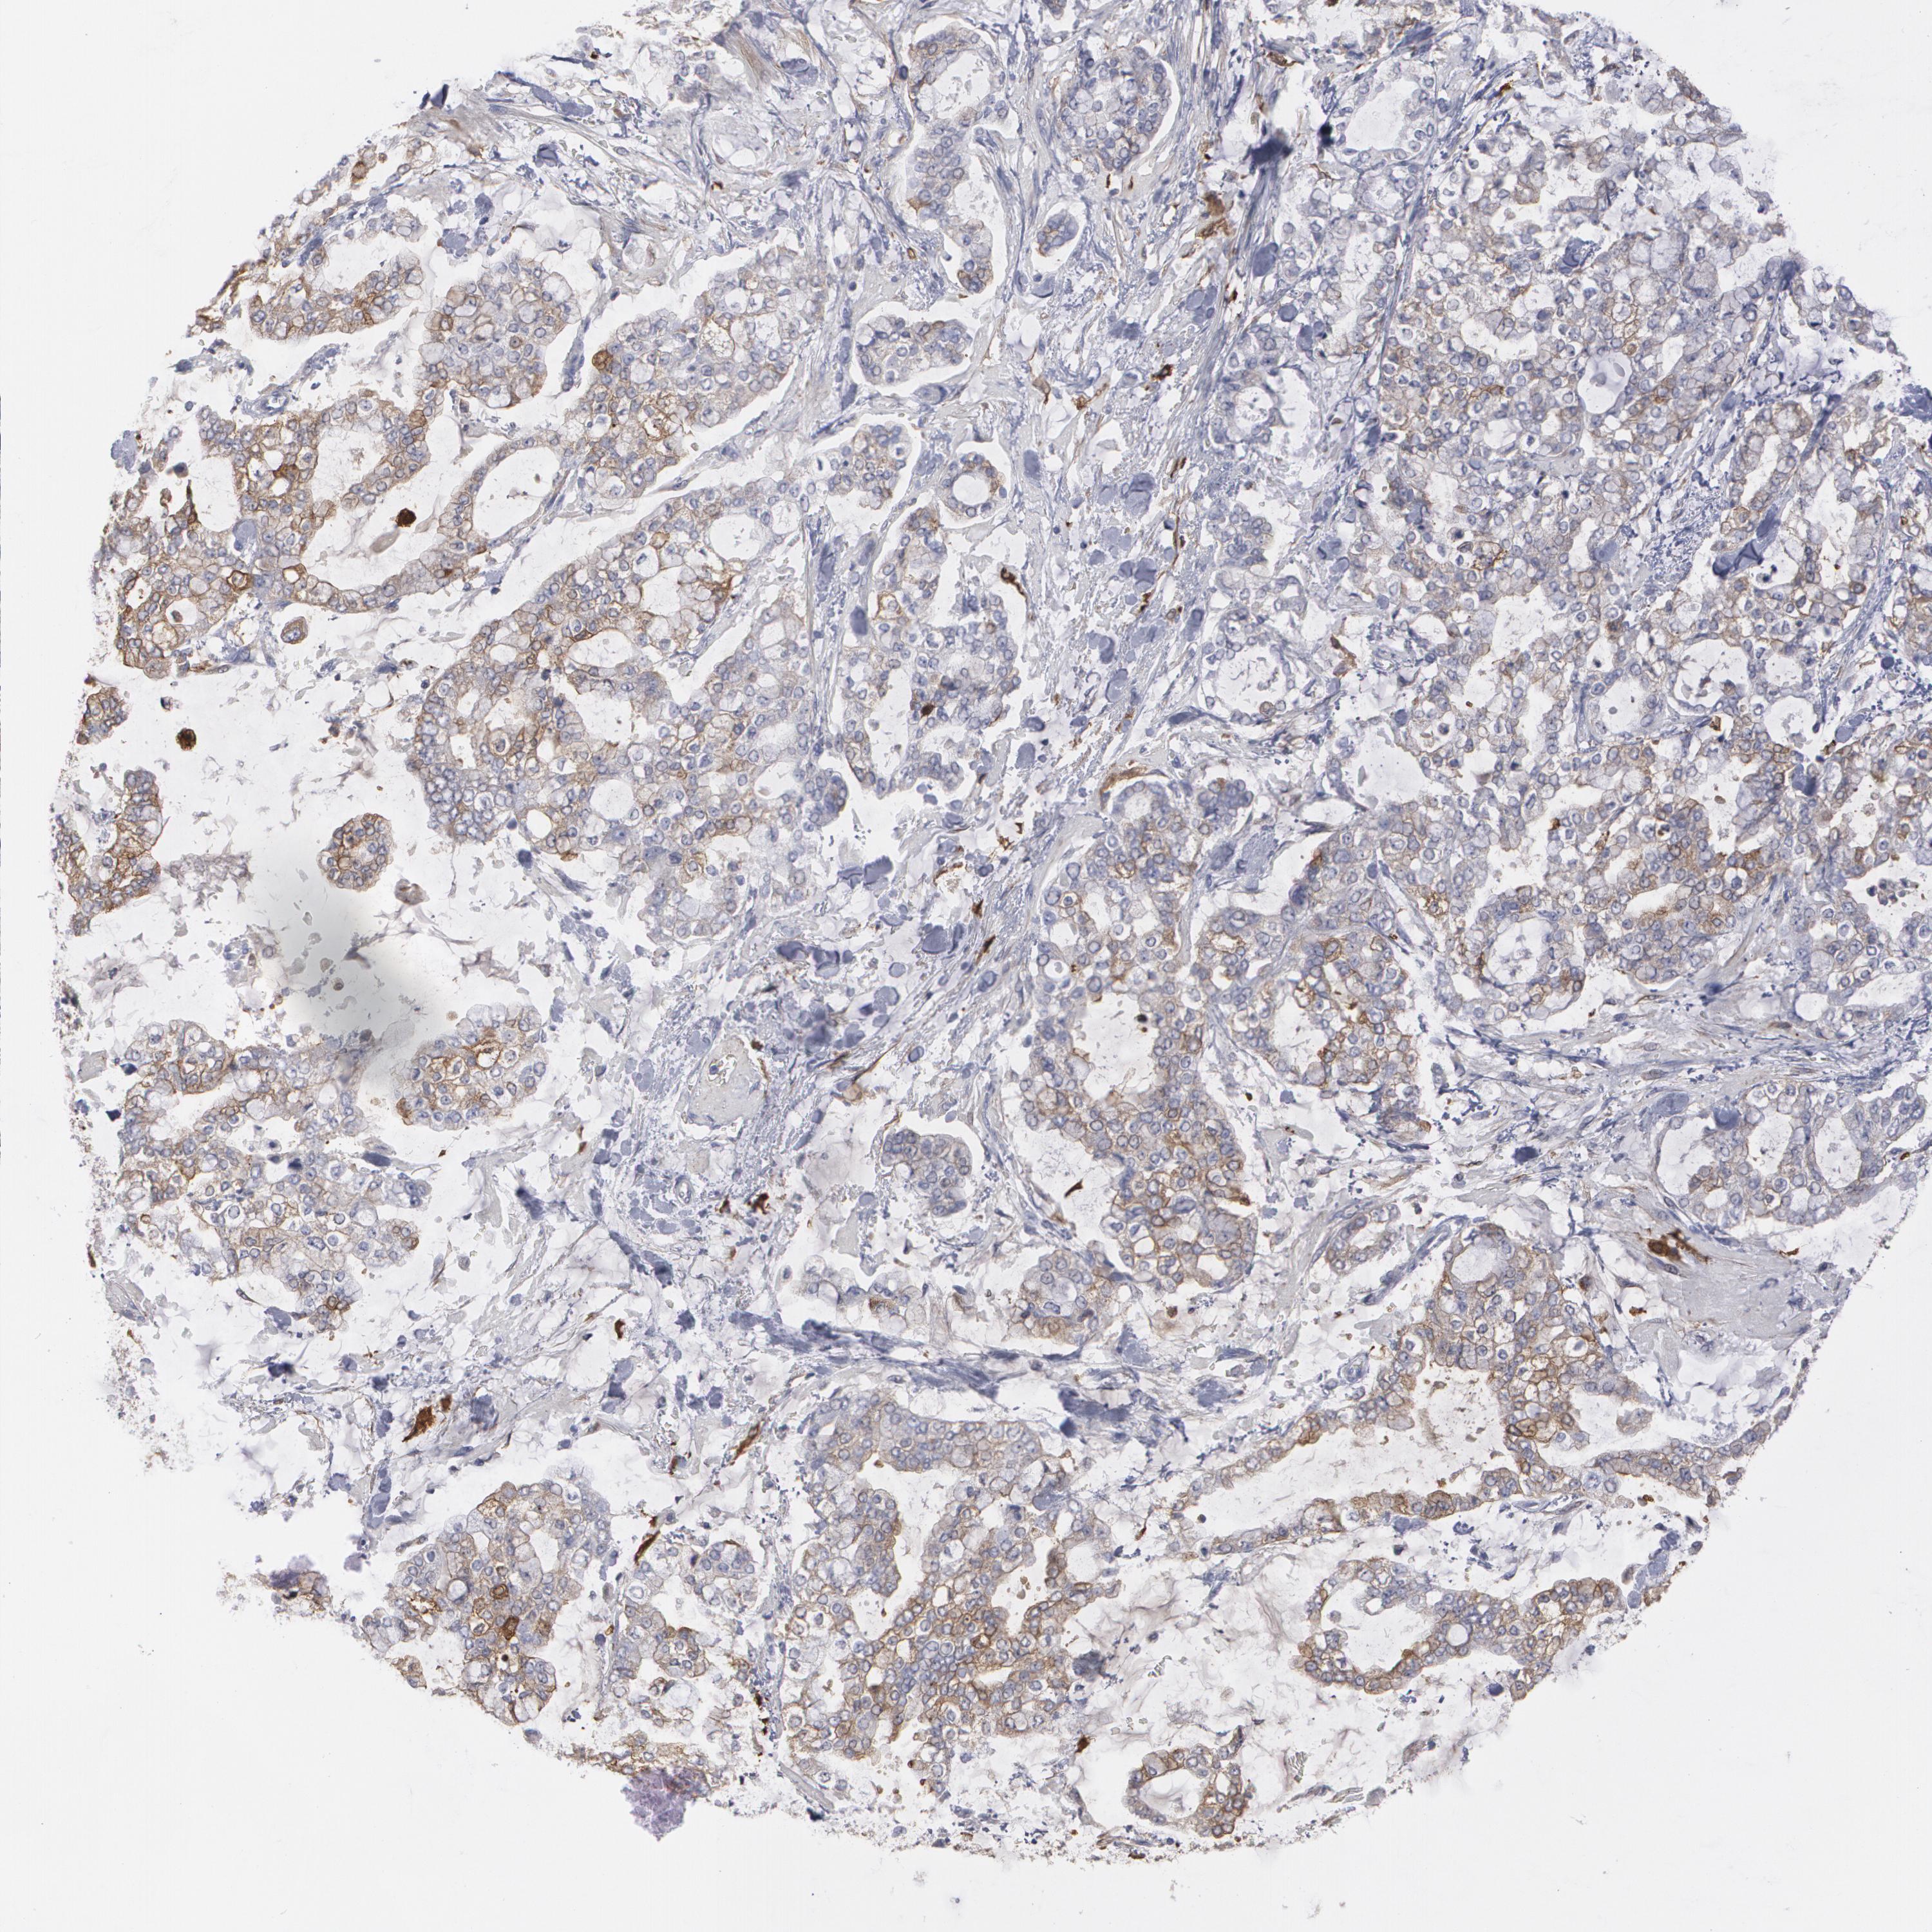

STOMACH CANCER - Protein expressioni

A mouse-over function shows sample information and annotation data. Click on an image to view it in a full screen mode. Samples can be filtered based on level of antibody staining by selecting one or several of the following categories: high, medium, low and not detected. The assay and annotation is described here.

Antibody stainingi

Antibody staining in the annotated cell types in the current human tissue is reported as not detected, low, medium, or high, based on conventional immunohistochemistry profiling in selected tissues. This score is based on the combination of the staining intensity and fraction of stained cells.

Each image is clickable and will lead to virtual microscopy that enables deeper exploration of all samples and also displays staining intensity scores, fraction scores and subcellular localization as well as patient and tissue information for each sample.

Antibody CAB035996

Staining

High

Medium

Low

Not detected

Intensity

Strong

Moderate

Weak

Negative

Quantity

>75%

75%-25%

<25%

None

Location

Nuclear

Cytoplasmic/membranous

Cytoplasmic/membranous,nuclear

Adenocarcinoma, NOS